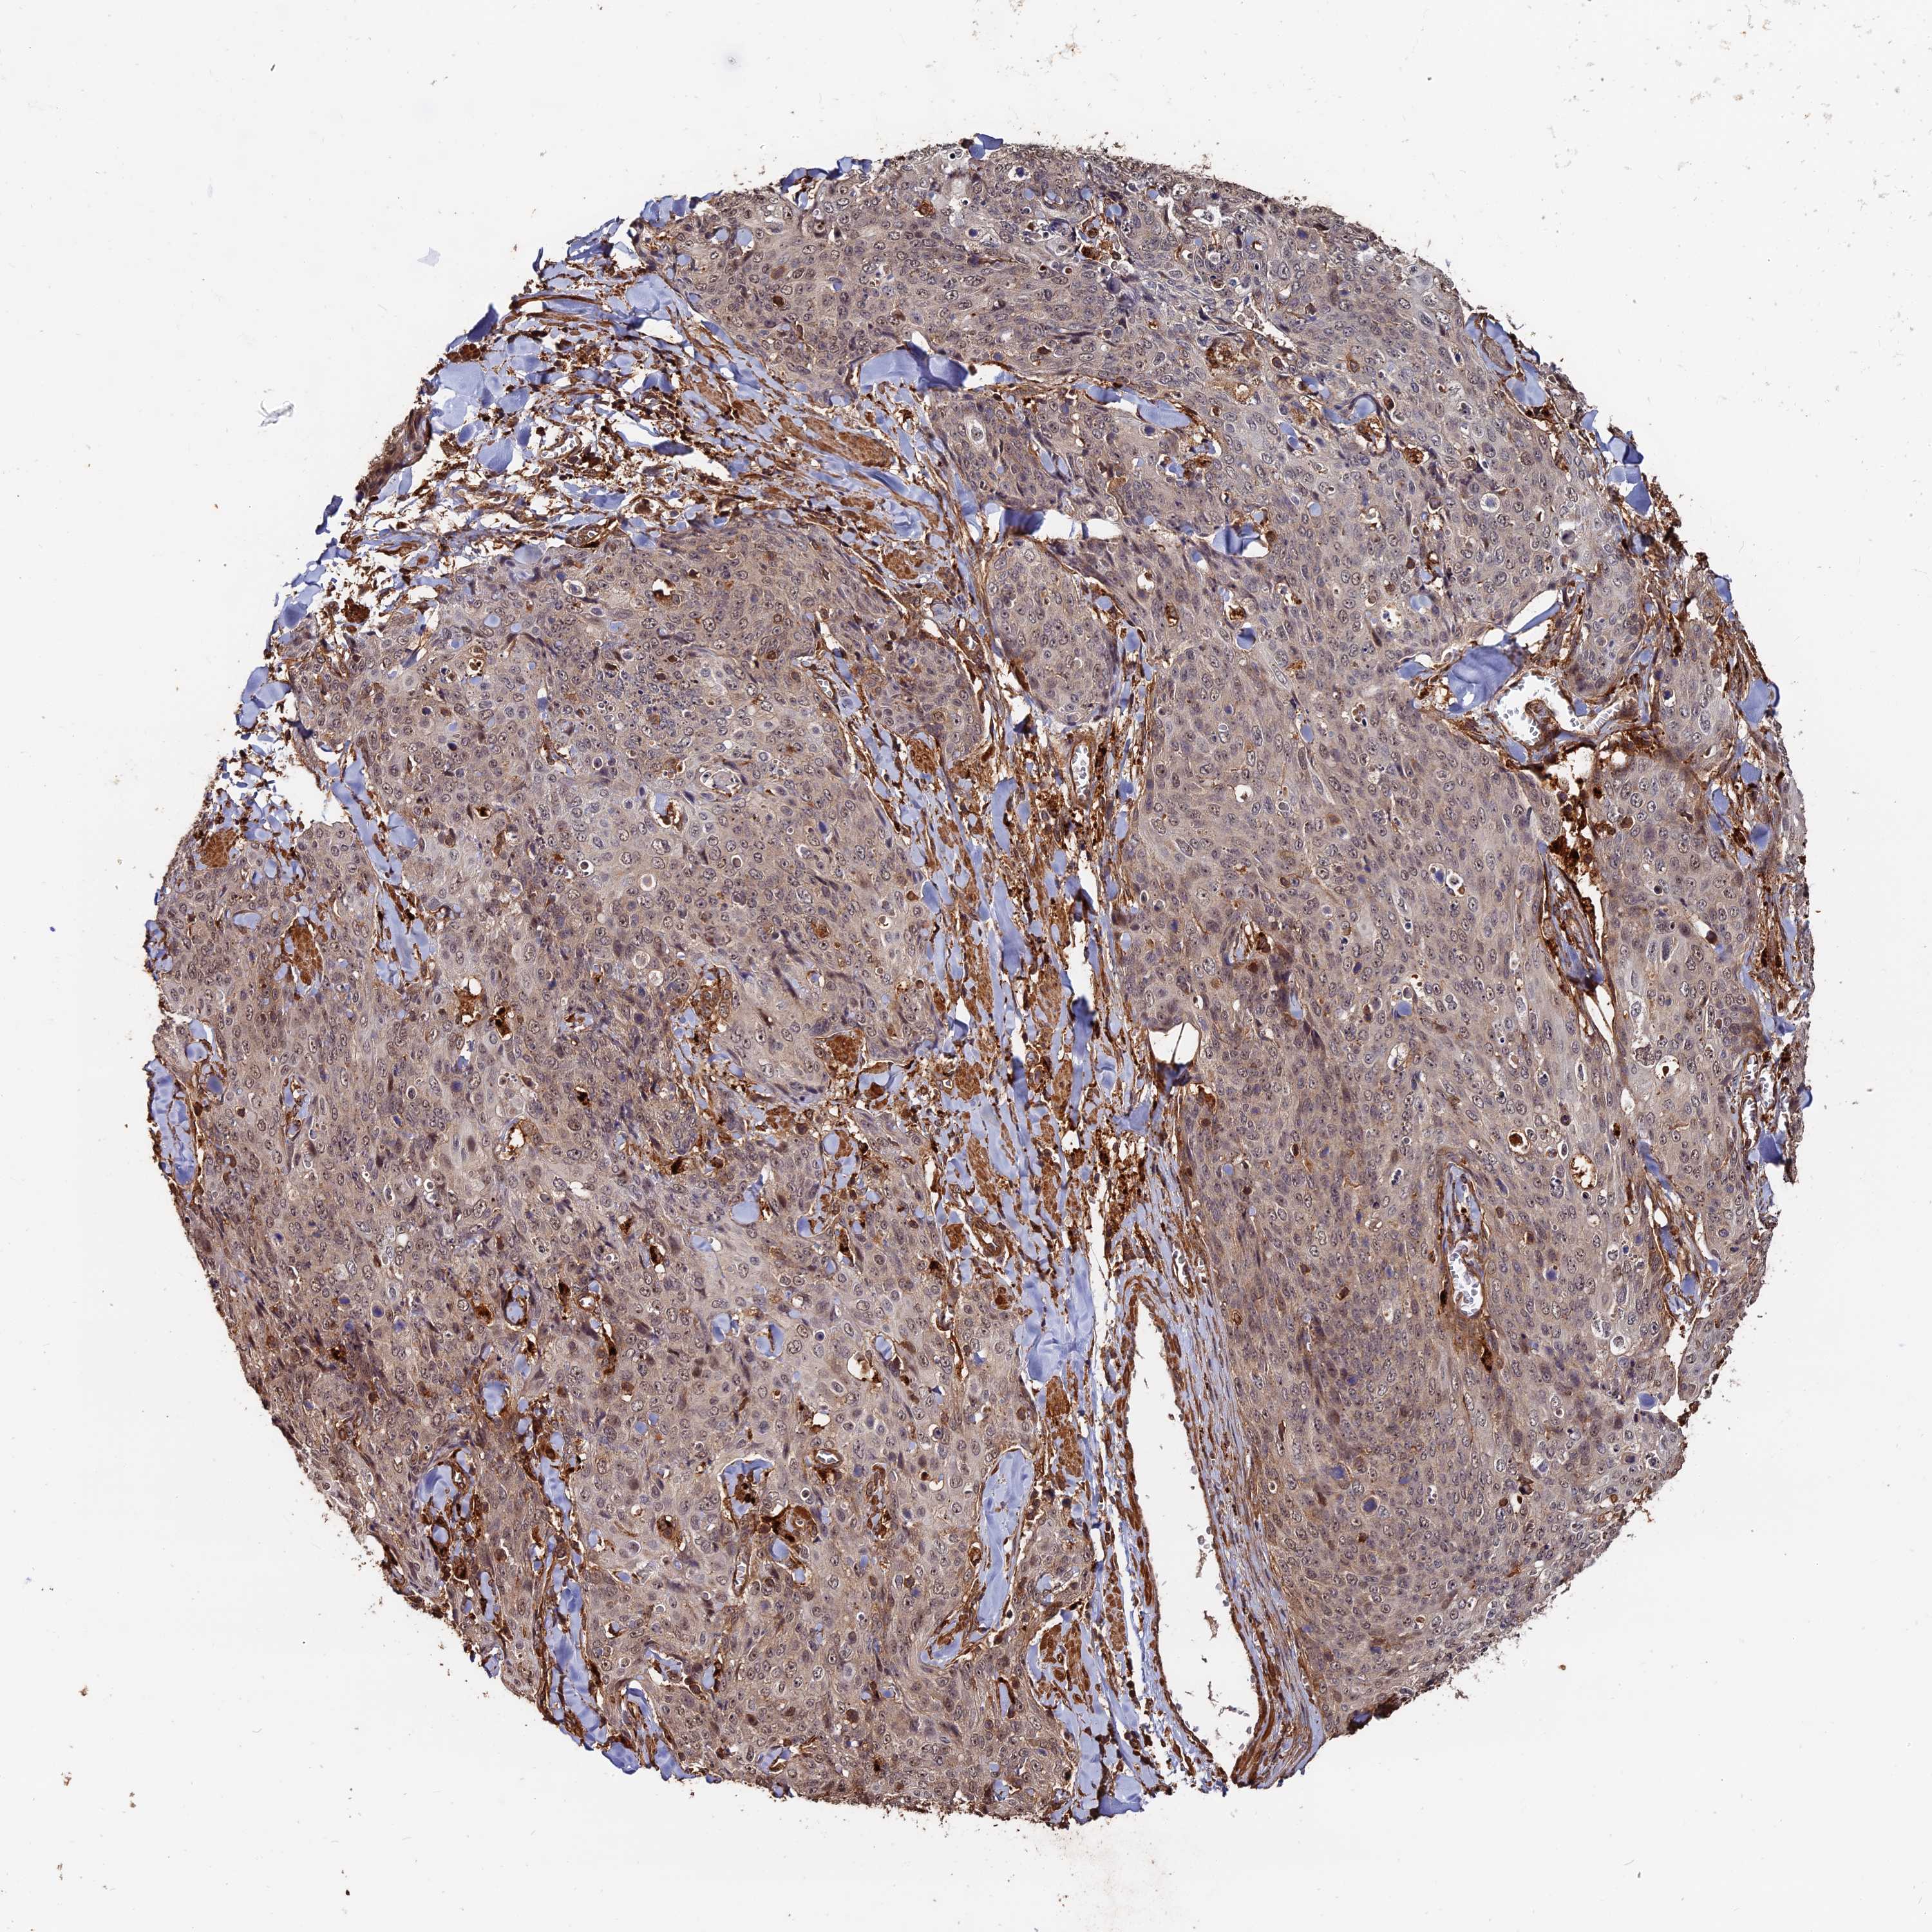

Basal cell and squamous cell cancer

SKIN CANCER - Protein expressioni

A mouse-over function shows sample information and annotation data. Click on an image to view it in a full screen mode. Samples can be filtered based on level of antibody staining by selecting one or several of the following categories: high, medium, low and not detected. The assay and annotation is described here.

Antibody stainingi

Antibody staining in the annotated cell types in the current human tissue is reported as not detected, low, medium, or high, based on conventional immunohistochemistry profiling in selected tissues. This score is based on the combination of the staining intensity and fraction of stained cells.

Each image is clickable and will lead to virtual microscopy that enables deeper exploration of all samples and also displays staining intensity scores, fraction scores and subcellular localization as well as patient and tissue information for each sample.

Antibody HPA040390

Antibody CAB002611

Squamous cell carcinoma, NOS